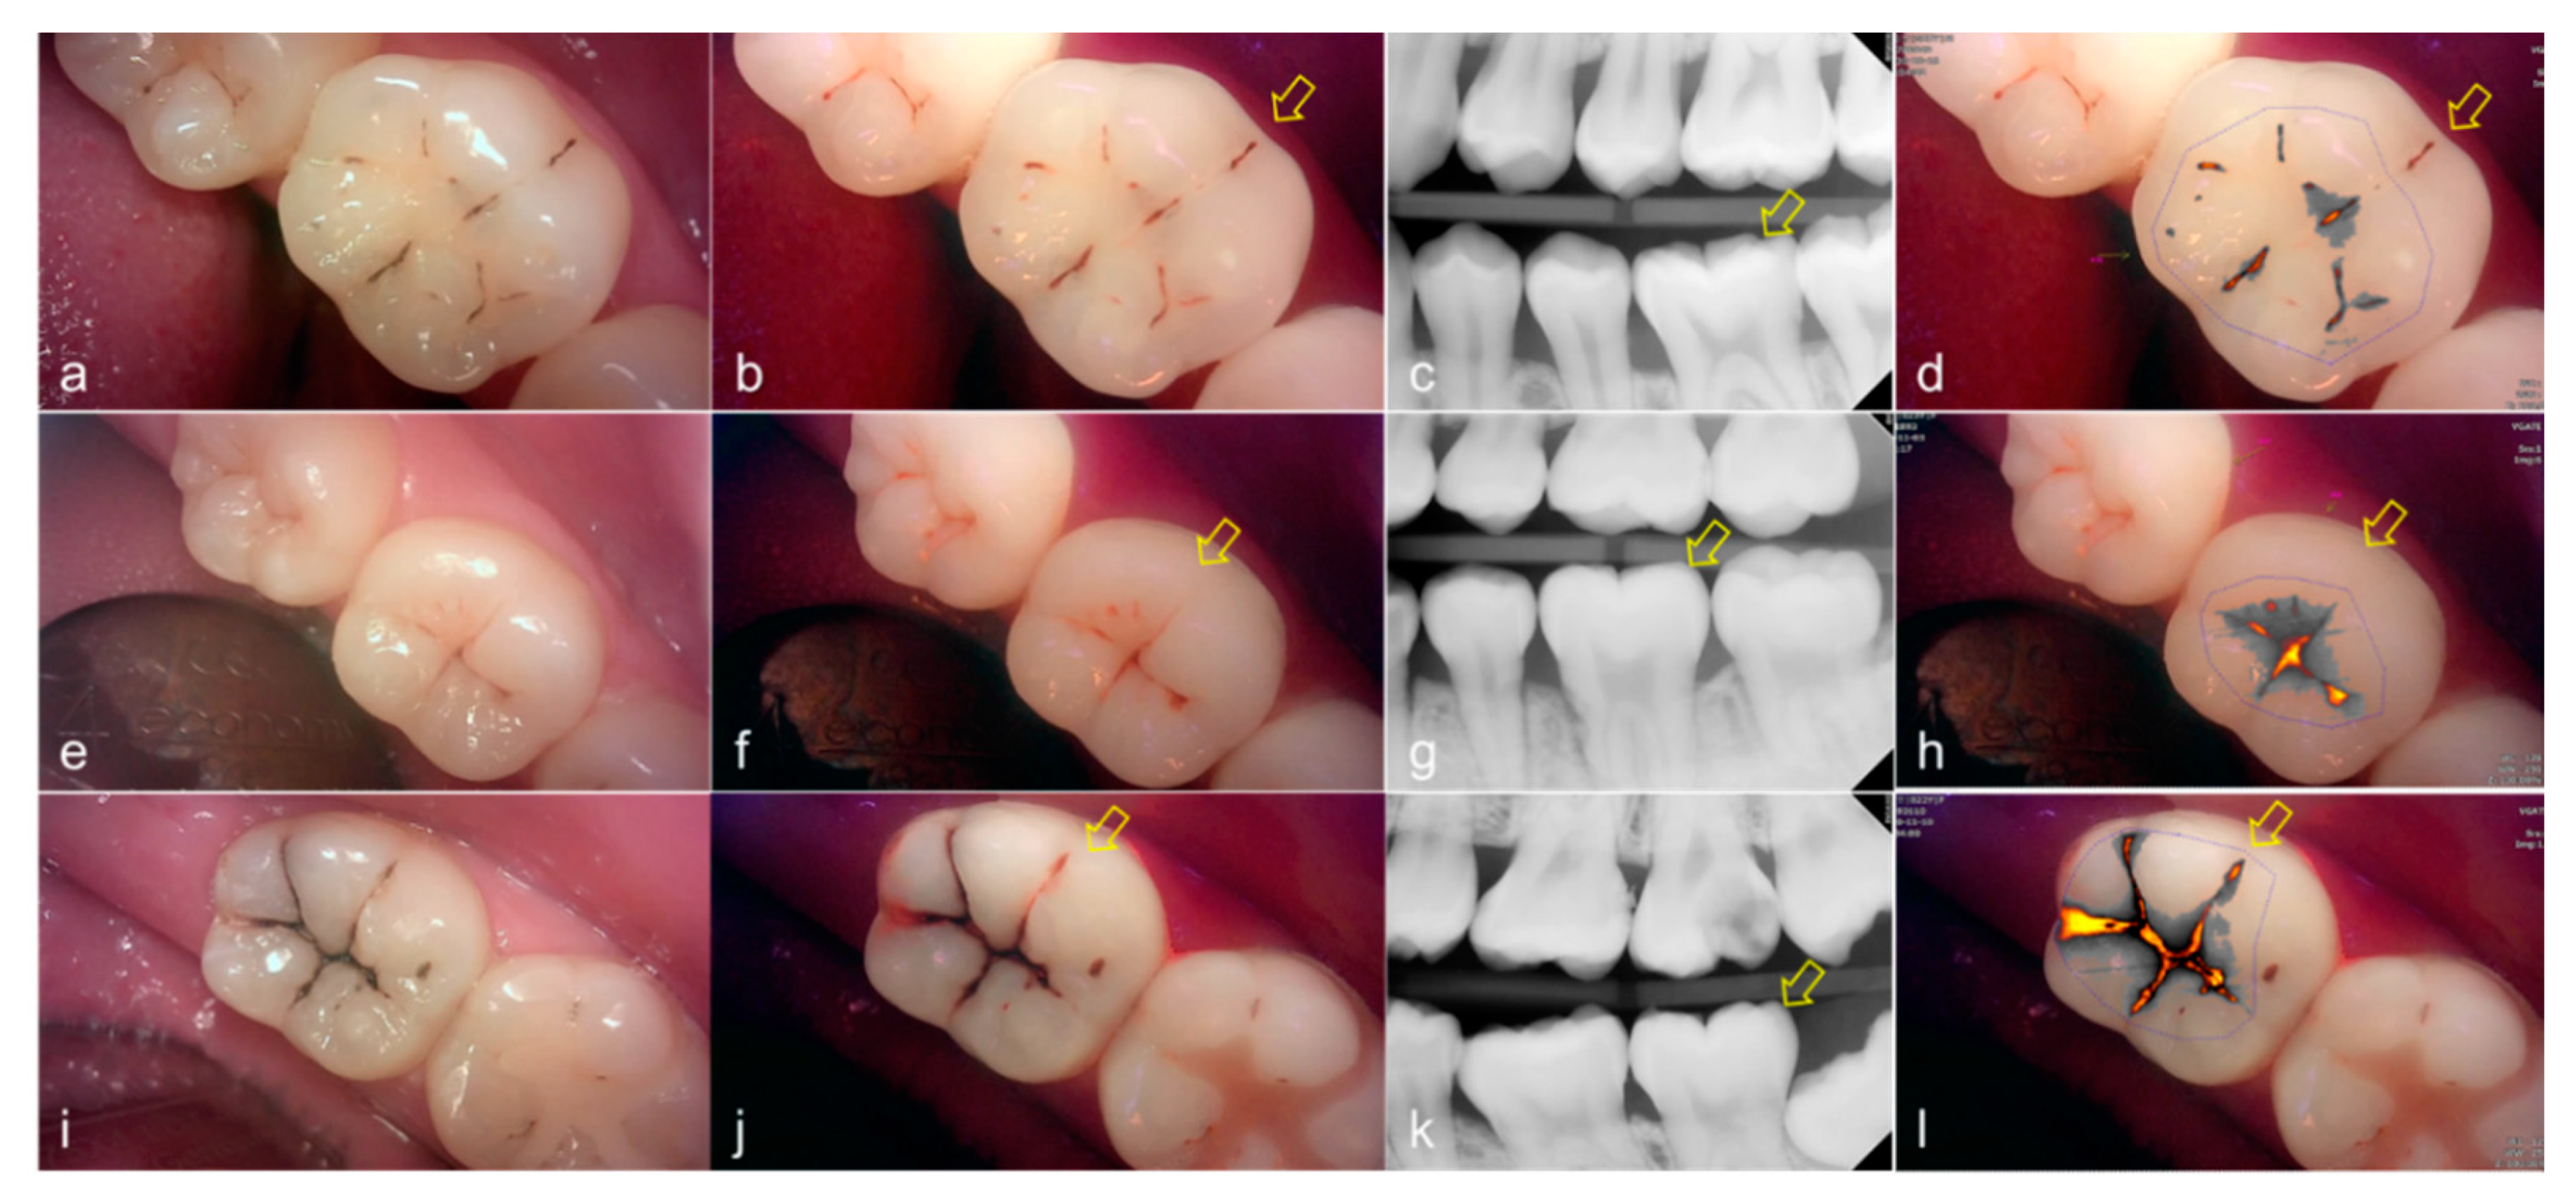

Figure 5.

Occlusal dental caries: (a–d) QLF caries score 2 (fluorescence loss and red fluorescence glow extending around pits and fissures) and radiographic caries score 3 (radiolucency extending to the middle 1/3 of the dentine) on #47; (e–h) QLF caries score 3 (red fluorescence glow extending around pits and fissures and a dark shadow from dentin present) and radiographic caries score 3 (radiolucency extending to the middle 1/3 of the dentine) on #37; (i–l) QLF caries score 3 (red fluorescence glow extending around pits and fissures and a dark shadow from dentin present) and radiographic caries score 3 (radiolucency extending to the middle 1/3 of the dentine) on #47; (a,e,i): white-light image of QLF; (b,f,j): fluorescence image of QLF; (c,g,k): bitewing radiograph; (d,h,l): analyzed QLF image using QA2 software.